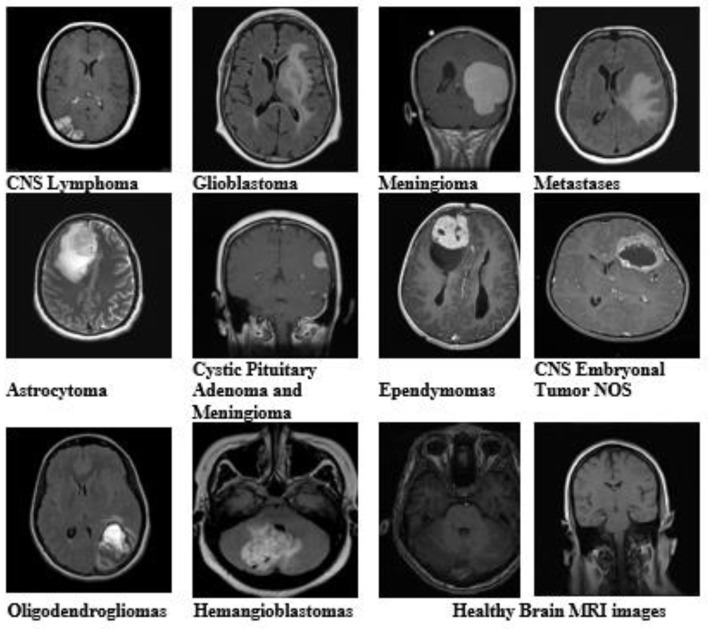

Corrigendum: An enhanced pattern detection and segmentation of brain tumors in MRI images using deep learning technique.